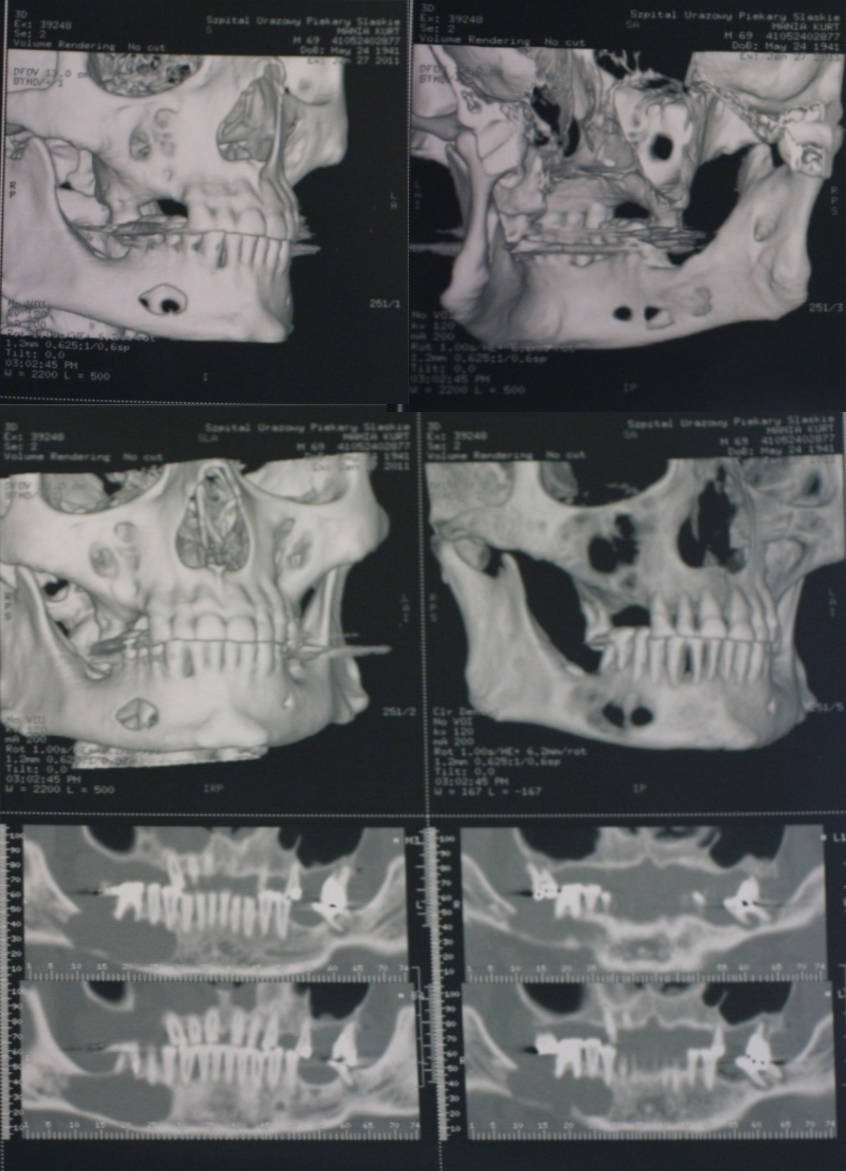

Antes de hablar de bisturí, miramos. Y miramos bien. Estudiamos la relación de la raíz con el nervio dentario inferior o el seno maxilar mediante radiografía periapical y, cuando aporta seguridad, CBCT en 3D. Analizamos angulación, profundidad y espacio disponible. Con esa “hoja de ruta” diseñamos un acceso conservador que minimiza riesgos y acorta la recuperación.

Diagnóstico previo: ver bien para decidir mejor

Antes de programar una quistectomía necesitamos una imagen nítida del problema. Empezamos con radiología 2D para ubicar la lesión y estimar su tamaño. Si intuimos cercanía al nervio dentario inferior o al seno maxilar, pasamos a CBCT: el 3D nos revela límites reales, tabiques, adelgazamientos corticales o expansión ósea. Con esa cartografía quirúrgica elegimos el acceso, anticipamos riesgos y definimos si conviene una fase previa de descompresión. Tras la exéresis, la pieza va siempre a anatomía patológica: el diagnóstico definitivo lo dicta la histología, no la radiografía.

Operamos cuando la lesión crece, se infecta de forma repetida o compromete dientes y estructuras vecinas. En cavidades muy grandes —especialmente en jóvenes— valoramos descompresión o marsupialización para reducir presión interna y favorecer la neoformación ósea, transformando una cirugía de alto riesgo en un procedimiento más seguro y predecible. Es una estrategia de pasos cortos, pero firmes.

Riesgos específicos y cómo los minimizamos

En mandíbula, el riesgo es la alteración sensorial del labio/mentón por cercanía al nervio; lo reducimos con CBCT, instrumentos finos y mínima tracción. En maxilar, cuidamos el sellado del seno y damos pautas de no presión (no sonarse, no succionar) durante los primeros días. También vigilamos la estabilidad de los dientes vecinos: si alguna raíz queda desprovista de hueso, planificamos su manejo (endodoncia, ferulización o restauración) para asegurar el pronóstico.